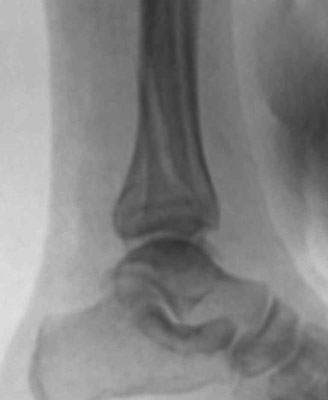

Im günstigsten Fall entsteht nur eine Verstauchung des Sprunggelenks mit Dehnung und Zerrung der Gelenkkapsel oder ein Riss der Bänder, die das Sprunggelenk stabilisieren (Außenbandriss). Bei den Knochenbrüchen handelt es sich fast immer um eine Kombination aus Knochenbrüchen und Verletzungen des Kapsel-/Bandapparates (Syndesmosenband, Innenband). Diese Kombinationen führen zu einer Instabilität der Sprunggelenksgabel mit Fehlstellung. Einfachste und häufigste Form ist der Bruch des Außenknöchels. Bei schwereren Verletzungen kommen Brüche des Innenknöchels und des sog. hinteren Knöchels dazu. Man spricht dann von „Zwei- oder Dreiknöchelbrüchen“ (Bimalleolär/Trimalleolär). Bei Zertrümmerung der Gelenkfläche des Schienbeins spricht man von einem „Pilon tibiale“.

Unverschobene und stabile Brüche können durch eine Stabilisierung im Gips oder Spezialschuh zur Ausheilung gebracht werden. Instabile und verschobene Brüche müssen operativ eingerichtet und stabilisiert werden, da es sonst durch Inkongruenzen und verbliebene Fehlstellungen zu einem schnellen Verschleiß (Arthrose) des Gelenkes kommt. Entscheidend für den Operationserfolg ist, das das sog. Sprungbein (Talus) wieder stabil und zentriert in der Sprunggelenksgabel geführt wird.